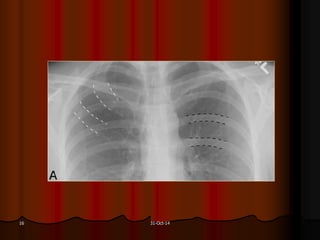

Được xem là hít đủ sâu khi ta thấy được hình chiếu của xương

sườn lên phổi 6 cung sườn trước hoặc 10 cung sườn sau.

31-Oct-1418

Hít không đủ sâu Hít đủ sâu